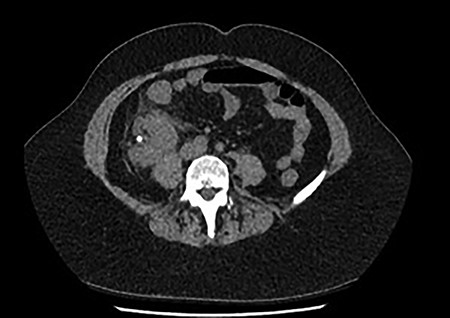

She was treated with ampicillin and a reduced dose of gentamicin given her AKI. Because of persisting shock, this patient was admitted to the intensive care unit (ICU) for inotropic support. Subsequently, both the urine and blood culture grew Escherichia coli. A repeat CT with contrast was performed due to persisting high fevers and severe right lower quadrant pain, which showed an early renal abscess (Fig. 2). Because of ongoing sepsis and absence of urology service in our hospital, the patient was transferred to another hospital where a urology service was available. She subsequently had insertion of a ureteric stent. The patient continued to improve post stent insertion and discharged when clinically well. She had removal of stone and ureteric stent 6 weeks later.

Progress CT showed worsening of perinephric inflammatory stranding and low-density area at the interpolar and upper pole of the right kidney representing an early renal abscess.